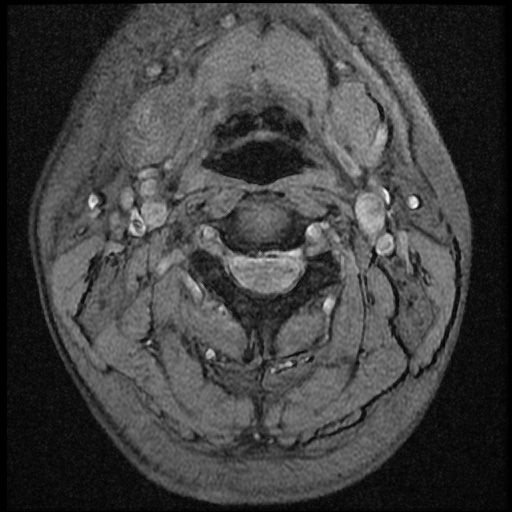

이 MRI 사진은 21년도 사고 당시 찍은 MRI 사진 입니다. 확인 부탁드립니다~

전체 mri를 다 봐여겠지만 보여주신 mri 컷에서는 의미있는 경추 디스크탈출이 보이지 않습니다.